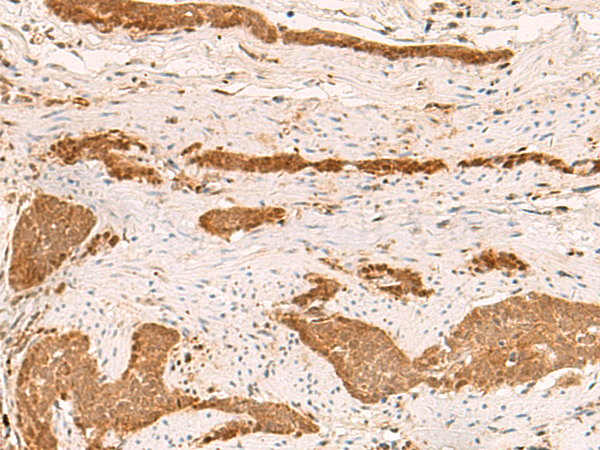

IHC (Immunohistochemistry)

(AAA323331 at 1/100 staining Human thyroid cancer tissue by IHC-P. The sample was formaldehyde fixed and a heat mediated antigen retrieval step in citrate buffer was performed. The sample was then blocked and incubated with the antibody for 1.5 hours at 22 degree C. An HRP conjugated goat anti-rabbit antibody was used as the secondary.)